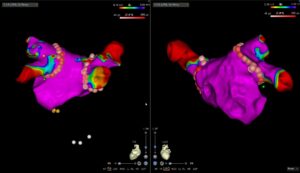

Eine bewährte Therapie bei verschiedensten Herzrhythmusstörungen, insbesondere wenn eine Rhythmuskontrolle erzielt werden soll, ist die Ablation mittels Spezialkatheter. Hierfür werden im Rahmen einer elektrophysiologischen Untersuchung (EPU) verschiedene Orte auf der Herzinnenseite, die für die Rhythmusstörungen verantwortlich sind, aufgesucht. Anschliessend wird die Elektrode des Katheters mit Hochfrequenzstrom erhitzt oder mittels Kälteabgabe angefroren. Die erzeugten Läsionen haben zum Ziel die Ausbreitung der elektrischen Impulse einzuschränken und somit die Rhythmusstörung zu eliminieren.

Eine bewährte Therapie bei verschiedensten Herzrhythmusstörungen, insbesondere wenn eine Rhythmuskontrolle erzielt werden soll, ist die Ablation mittels Spezialkatheter. Hierfür werden im Rahmen einer elektrophysiologischen Untersuchung (EPU) verschiedene Orte auf der Herzinnenseite, die für die Rhythmusstörungen verantwortlich sind, aufgesucht. Anschliessend wird die Elektrode des Katheters mit Hochfrequenzstrom erhitzt oder mittels Kälteabgabe angefroren. Die erzeugten Läsionen haben zum Ziel die Ausbreitung der elektrischen Impulse einzuschränken und somit die Rhythmusstörung zu eliminieren.

Typische Herzrhythmusstörungen, welche mittels Ablation behandelt werden können, sind:

- Vorhofflimmern (Abb 1 und 2)

- Vorhofflattern

- AV Knoten Reentrytachykardie

- Wolf-Parkinson-White Syndrom (WPW)

- Fokal atriale Tachykardien

- Kammer-Extraschläge

- Kammertachykardien

Die Erfolgschance einer Ablation hängt von vielen Faktoren ab, inkl. der Rhythmusstörung selber sowie allfälligen Begleiterkrankungen etc. In einem persönlichen Gespräch diskutieren wir mit Ihnen die sie bietenden Möglichkeiten und erstellen einen individuellen Therapieplan.

Abbildungen:

Abb 1 und 2: Vorhofflimmern Ablation mit 3D-Mapping System

Eine bewährte Therapie bei verschiedensten Herzrhythmusstörungen, insbesondere wenn eine Rhythmuskontrolle erzielt werden soll, ist die Ablation mittels Spezialkatheter. Hierfür werden im Rahmen einer elektrophysiologischen Untersuchung (EPU) verschiedene Orte auf der Herzinnenseite, die für die Rhythmusstörungen verantwortlich sind, aufgesucht. Anschliessend wird die Elektrode des Katheters mit Hochfrequenzstrom erhitzt oder mittels Kälteabgabe angefroren. Die erzeugten Läsionen haben zum Ziel die Ausbreitung der elektrischen Impulse einzuschränken und somit die Rhythmusstörung zu eliminieren.

Typische Herzrhythmusstörungen, welche mittels Ablation behandelt werden können, sind:

- Vorhofflimmern (Abb 1 und 2)

- Vorhofflattern

- AV Knoten Reentrytachykardie

- Wolf-Parkinson-White Syndrom (WPW)

- Fokal atriale Tachykardien

- Kammer-Extraschläge

- Kammertachykardien

Die Erfolgschance einer Ablation hängt von vielen Faktoren ab, inkl. der Rhythmusstörung selber sowie allfälligen Begleiterkrankungen etc. In einem persönlichen Gespräch diskutieren wir mit Ihnen die sie bietenden Möglichkeiten und erstellen einen individuellen Therapieplan.

Abbildungen:

Abb 1 und 2: Vorhofflimmern Ablation mit 3D-Mapping System